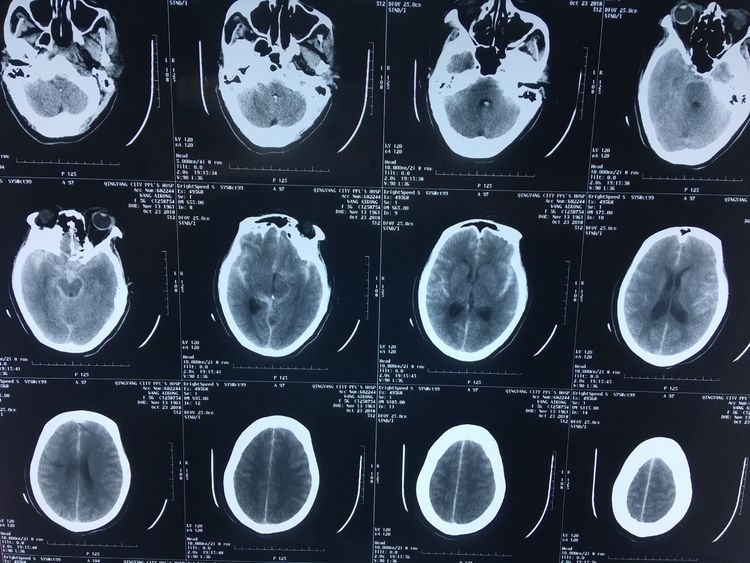

患者,女52岁,突发头痛头晕伴恶心到市人民医院就诊,CT提示珠网膜下腔出血,随收住神经外科。急诊在我院神经外科介入室行全脑血管造影,发现左侧颈内动脉后交通段一大小约23mmx17mm巨大动脉瘤。右侧大脑前动脉未见显示,供血区由左侧大脑前动脉代偿供血,后循环系统右侧椎动脉优势供血。

经科室会诊、与家属充分沟通,在上级专家指导下行颅内动脉瘤弹簧圈栓塞+支架植入术,术中支架释放顺利。术毕造影:瘤腔栓塞致密,瘤颈未见残留,支架贴壁良好,各级血管分支分布未见缺失,供血良好,手术顺利完美结束。目前患者已康复出院。